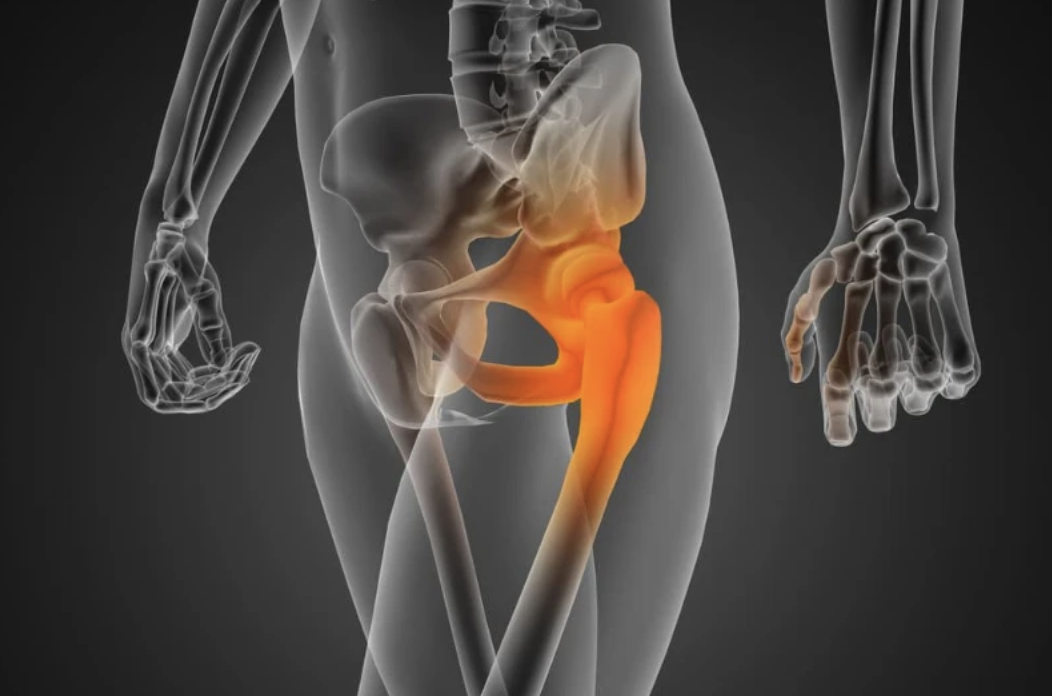

La tendinopatía glútea afecta a los tendones que conectan la musculatura de los glúteos (alrededor de la articulación de la cadera).

Entre ellos se encuentran el músculo glúteo mayor, el glúteo medio y menor, la musculatura isquiotibial y la musculatura cuadricipital, entre otras.

Estos músculos y tendones van desde el hueso de la cadera (pelvis) hasta el trocánter mayor. El trocánter mayor es la cresta que se encuentra en la parte superior del hueso del muslo (fémur).

La bursa trocantérea se encuentra en la parte externa de la cadera, sobre el hueso prominente llamado trocánter mayor, que se encuentra en la parte superior del fémur.

Una de las causas más comunes del dolor de cadera es la inflamación de la parte lateral o cerca de trocánter mayor.

La coxartrosis está causada por el desgaste del cartílago de la cabeza del fémur y de la cavidad articular de la pelvis que posee un hueco para que formen un engranaje, y permitir el movimiento del fémur en múltiples direcciones.